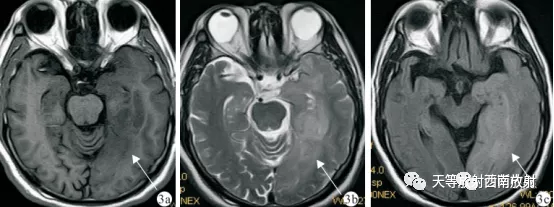

▲病例:脑间质瘤 上图 3a.T1WI肿瘤呈稍低信号或等信号,边界不清(白箭)3b. T2WI 肿瘤呈稍高信号,范围较T1WI范围更大(白箭)。3c. FLAIR T2WI示病灶呈片状稍高信号,以白质改变为主,灰质部分受累,信号比较均匀,邻近的脑沟、脑室弥漫性缩小,脑回和脑白质肿胀(白箭)。